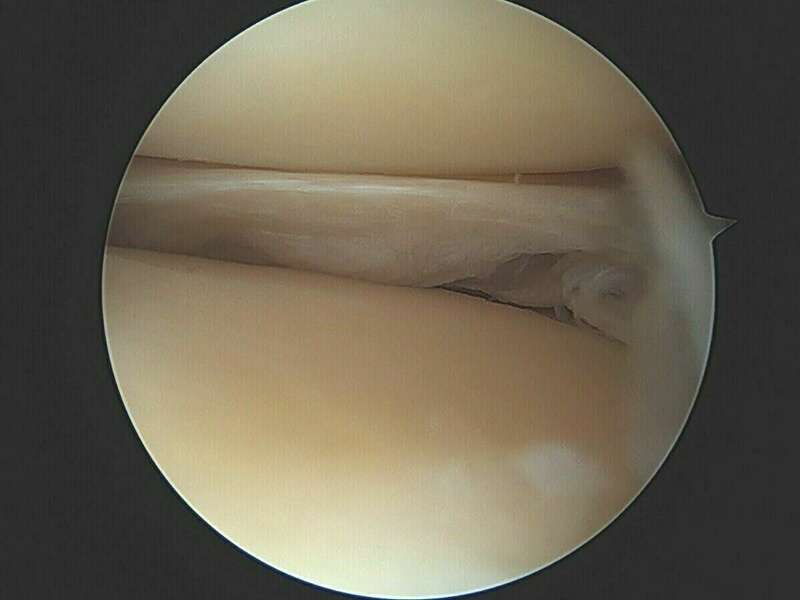

La ménisectomie sous arthroscopie vise à réséquer une lésion méniscale symptomatique tout en conservant un maximum de ménisque sain. L'arthroscopie permet d’explorer l'intérieur du genou, de faire un diagnostic et de traiter des lésions, en particulier méniscales et ligamentaires.

L'Arthroscope est un tube de quelques millimètres de diamètre, muni d'un système optique et d’un système d'éclairage, il est couplé à une caméra vidéo miniaturisée, elle-même reliée à un écran de télévision couleur. Il est mis en place à l'intérieur du genou par un orifice minime, un ou parfois plusieurs autres petits orifices cutanés sont nécessaires pour l'introduction d'instruments fins dans l'articulation. Pendant tout l'examen, le genou est gonflé avec du liquide (sérum physiologique).

L'arthroscopie permet de regarder : la cavité articulaire, les ménisques (interne et externe), le cartilage (de la rotule, du fémur, du tibia), la membrane synoviale (poche qui entoure l’articulation), et les ligaments croisés. Elle permet de réaliser une cartographie lésionnelle de votre genou.

De grandes avancées technologiques ont vu le jour ces-dernières années. L'utilisation d’instruments miniaturisés de haute précision permet désormais d’effectuer des méniscectomies « a minima » pour conserver un maximum de ménisque sain.

Album photo